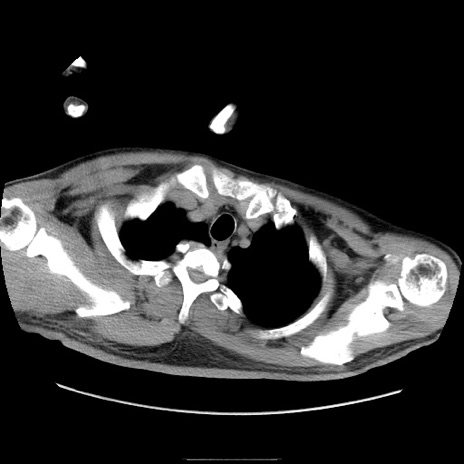

症例22(横断像)

【症例】50歳代男性

【主訴】腹痛

【現病歴】AVMからの被殻出血のため回復期リハ病棟入院中。 本日午後3時頃急に下腹部痛が出現した。

【既往歴】AVM、被殻出血、虫垂炎、高血圧

【身体所見】意識晴明、左半身不全麻痺、会話の理解は良好、36.5°C、腹部:膨隆、全体に板状硬、下腹部正中に圧痛点あり、反跳痛-、筋性防御不明、右下腹部にope scar

【データ】WBC 9400、CRP 0.06